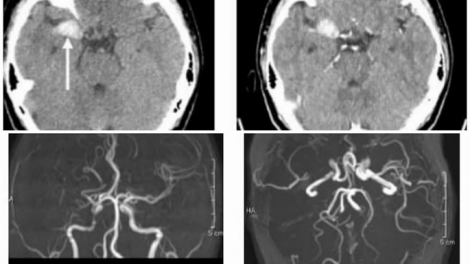

- Gia tăng bệnh nhân nhập viện do rét đậmbr> - Dịch sốt xuất huyết lây lan nhanh ở Brazil ,br> - Nhóm người có nguy cơ cao cần tiêm chủng đầy đủ để ngừa biến thể JN.1 - Bác sĩ Bệnh viện đa khoa Bình Định nghiên cứu công nghệ điều trị nhồi máu não cấp